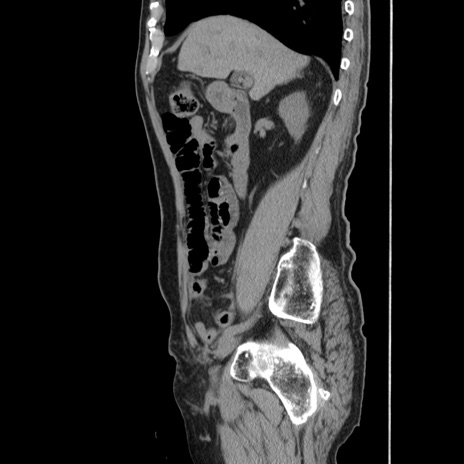

症例24(矢状断像)

【症例】80歳代男性

【主訴】左側腹部痛、嘔吐

【現病歴】本日早朝より左腹部に痛みあり。昼頃嘔吐認めたため、救急要請。

【既往歴】直腸癌(Mile手術)、胆摘

【身体所見】意識清明、BT 35.9℃、BP 221/93mmHg、SpO2 97%(RA) 、腹部:左ストーマ周囲に限局性の腹部膨隆あり。 膨隆部自発痛・圧痛あり・軟。

【データ】WBC 7700、CRP 0.09